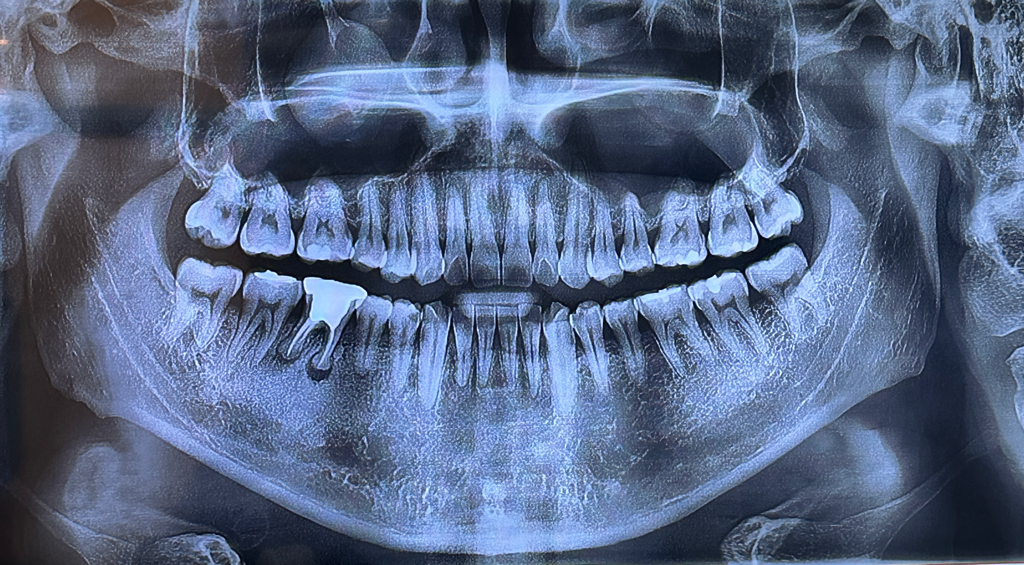

어차피 해야할것같아서 이를 뽑았는데요

곤봉부분 치아가 통증은 없었는데

무조건 임플란트를 하기는 해야되는 치아였을까요..?

사진상으로 보면 발치를 하셧어야 될 치아엿던거 같습니다. 하얗게 된부분은 잇몸이 치유되면서 자연스럽게 생기는 현상입니다.

1. 신경치료 전 사진이 있었다면 비교가 가능하겠으나 현재 상태로는 해당 치아 뿌리끝으로 염증이 잡혀있고, 치아 뿌리끝 섬유골성 병소도 존재합니다. 아마 재신경치료를 한다고 하더라도 회복되기 어려운 케이스가 아니였을까 싶습니다

2. 발치 부위에 대한 평가는 사진이 있다면 좀 더 정확할 것 같습니다. 현재 발치하고 3일차라면 혈병(피떡)에서 새로운 조직들이 활발하게 생성될 시기입니다.